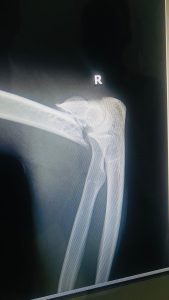

Yagize ati” Irondo ryari riyobowe na Habimana Jean Baptiste ryankuye iwanjye mu rugo kubera intonganya nari mfitanye n’umugore wanjye ndetse n’uwari aducumbikiye witwa Bahigubusa Gabriel bita Shatikoti, aribwo irondo ryanjyanye ku murenge wa Cyuve ryangezayo rigatangira kunkubita bya kinyamaswa bikamviramo kuvunika igufa ry’ukuboko nkanahafungirwa ariko nkaza kurekurwa mu gitondo.”

Yakomeje agira ati ” Nahise njya kwivuza kwa muganga mu bitaro bikuru bya Ruhengeri, aho nageze ngashyirwaho isima ariko igufa ryarangiritse. Nahise ntanga n’ikirego kuri RIB ariko kubera gukomeza kuremba, isima bayikuyeho basanga igufa ryaracitse, bityo biba ngombwa ko mpabwa taransiferi(Transfert) mu bitaro byisumbuyeho(Kigali) ari naho ngiye kwivuriza ariko nta bushobozi mfite.”